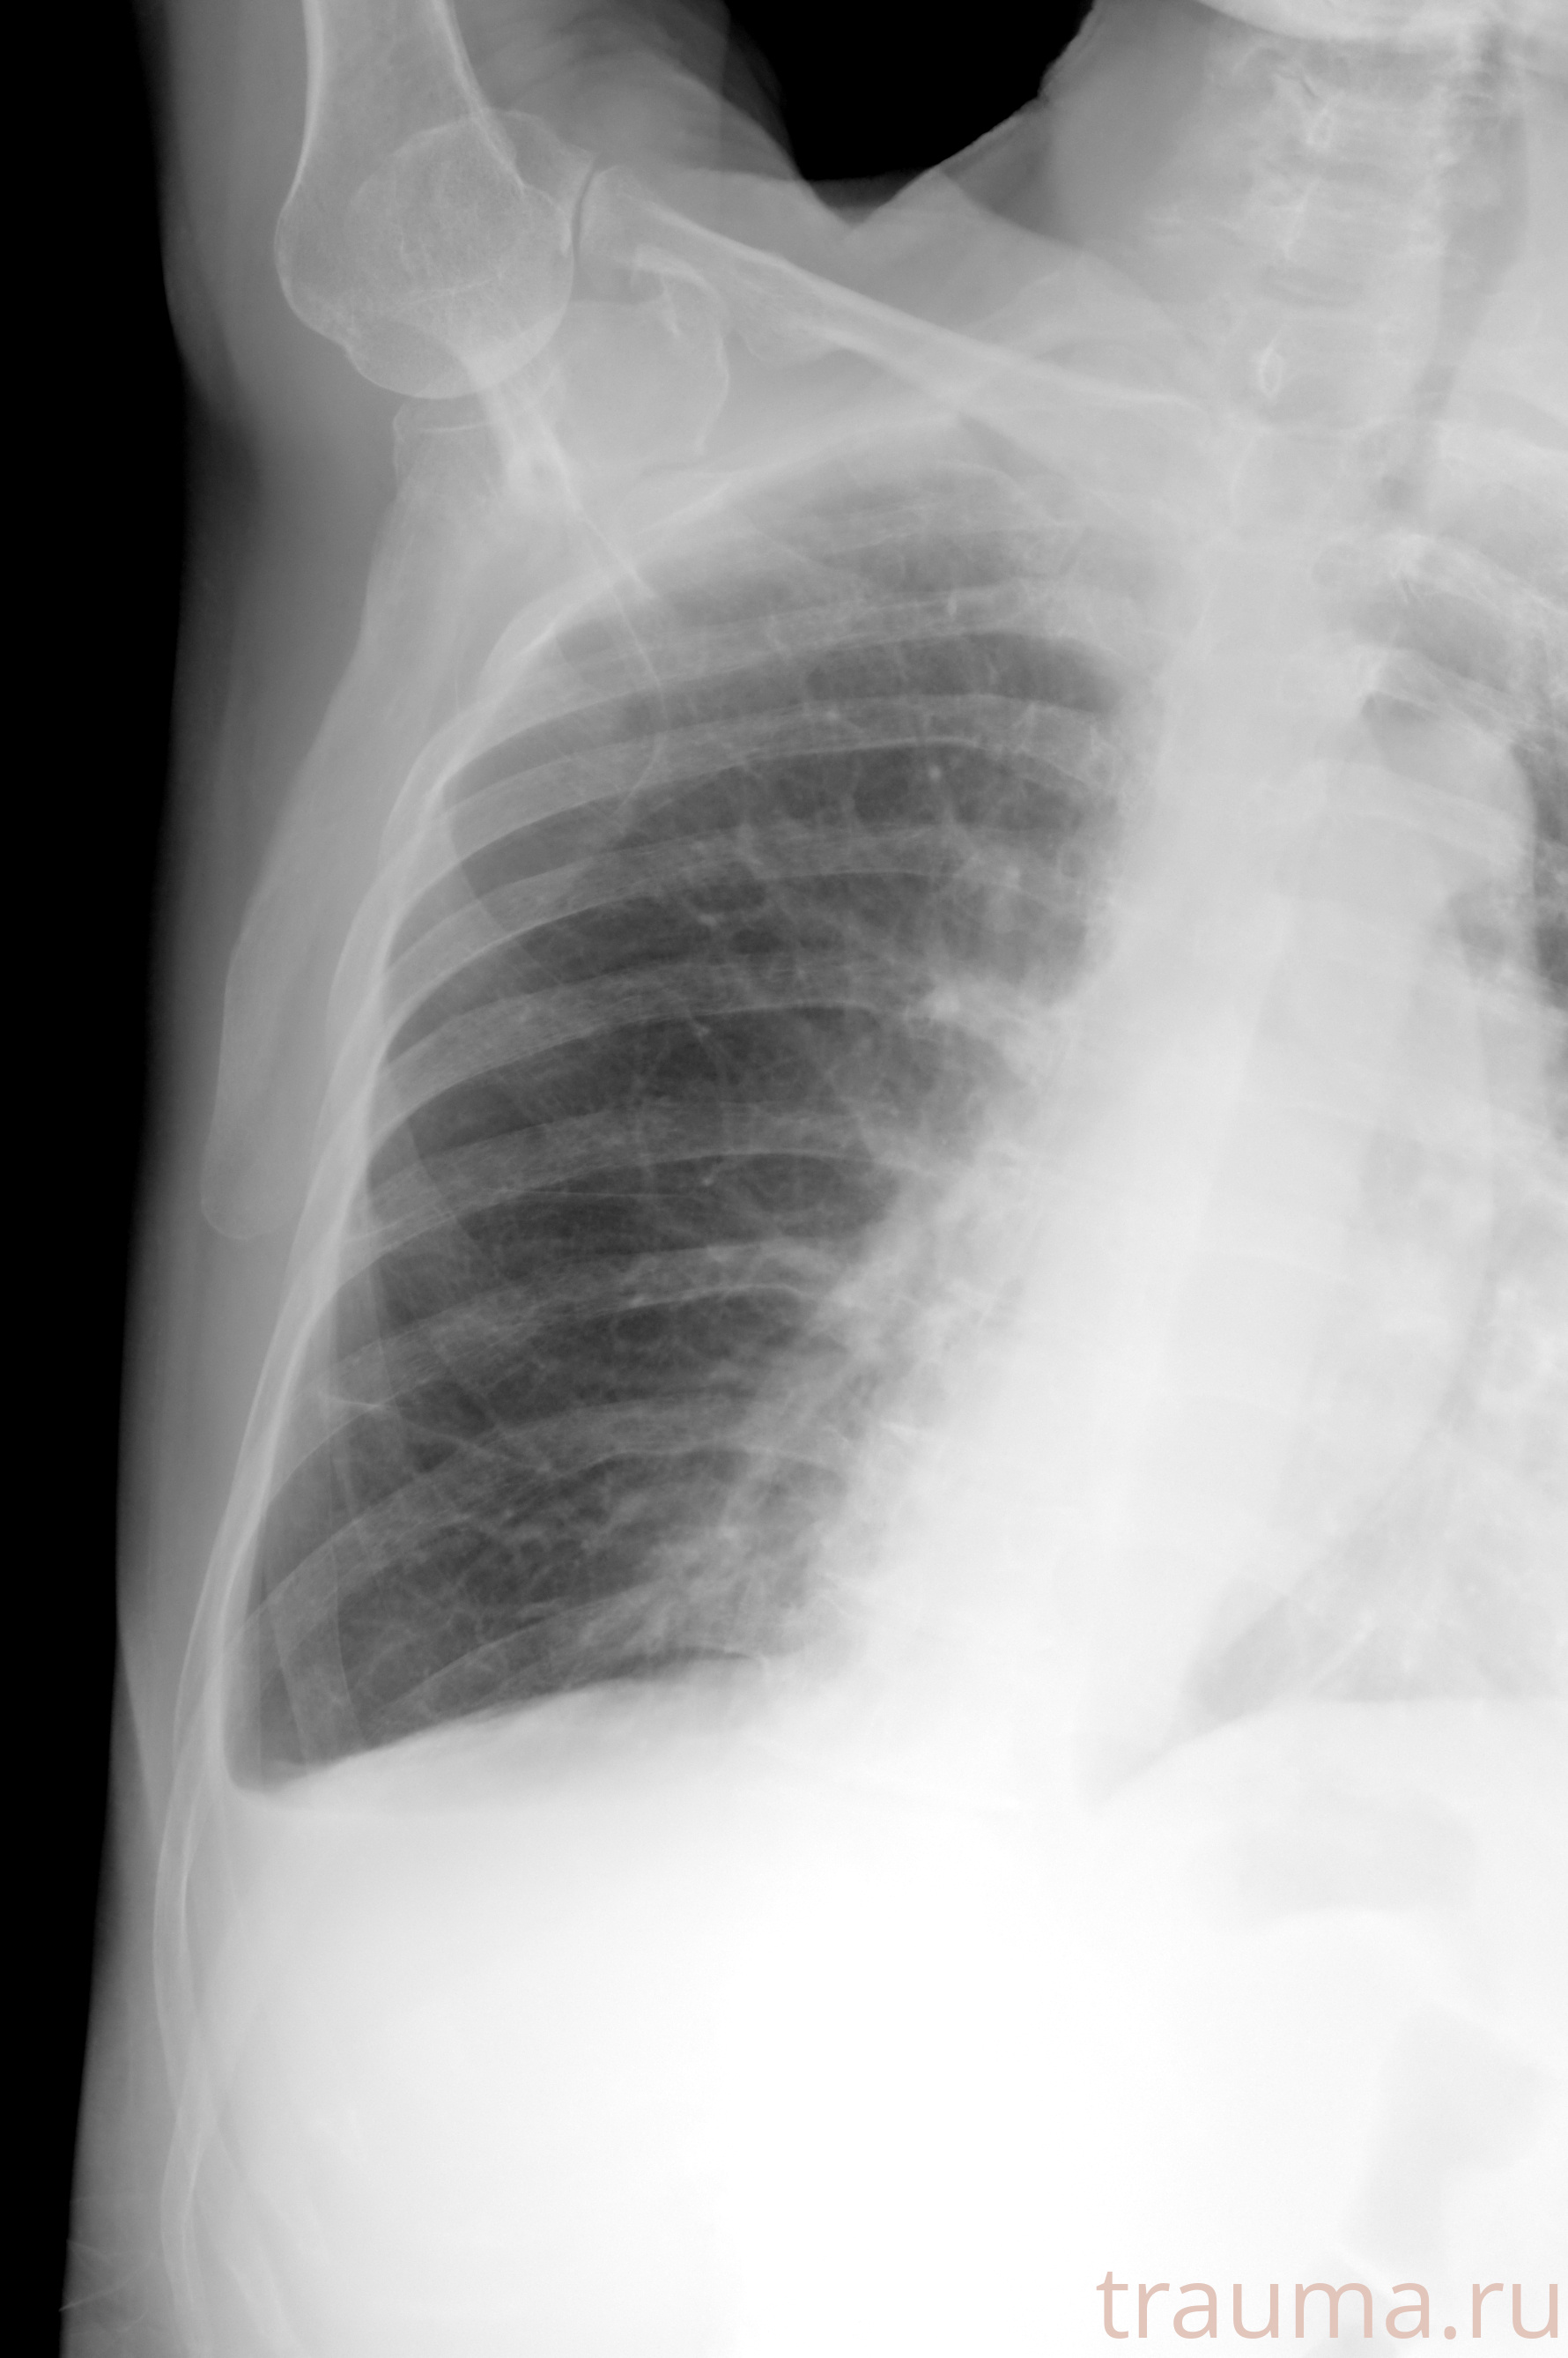

Рентгенограммы

Натуживание 26.12.2025 21:16:34